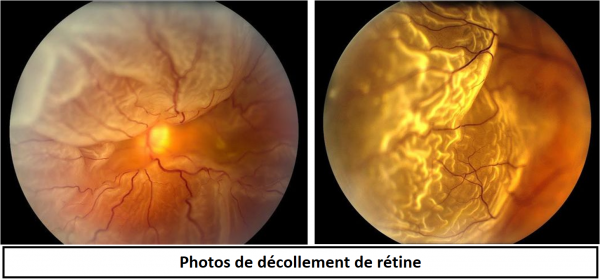

decollement retine photo Décollement de rétine

www.retinegallien.comDécollement De Rétine 03 | Le Magazine Santé

www.retinegallien.comDécollement De Rétine 03 | Le Magazine Santé